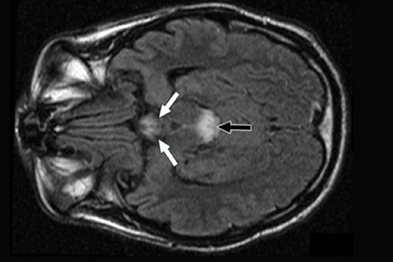

سندرم Wernicke-Korsakoff یک اختلال است که بر روی افراد مبتلا به مصرف مزمن الکل تاثیر می گذارد. این سندرم با کمبود تیامین ارتباط دارد و اگر درمان نشود، می تواند کشنده باشد. افراد مبتلا به سندرم Wernicke-Korsakoff و افرادی که الکل را ترک می کنند ممکن است بتوانند از تزریق تیامین برای کمک به بهبودی خود استفاده کنند.

سندرم Wernicke-Korsakoff یک اختلال است که بر افرادی که الکل زیاد می نوشند تاثیر می گذارد. این بیماری به کمبود تیامین ارتباط دارد و اگر درمان نشود، می تواند مرگبار باشد.

افراد مبتلا به سندرم Wernicke-Korsakoff و کسانی که الکل دفع می کنند ممکن است برای بهبود به تزریق تیامین روی آورند.